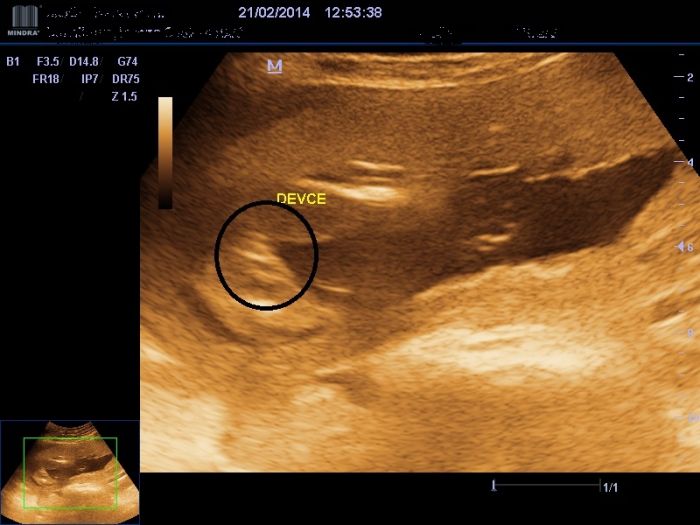

no tam kde je ta šipka tak to je prý penis? a to na těch stranách jsou stehna